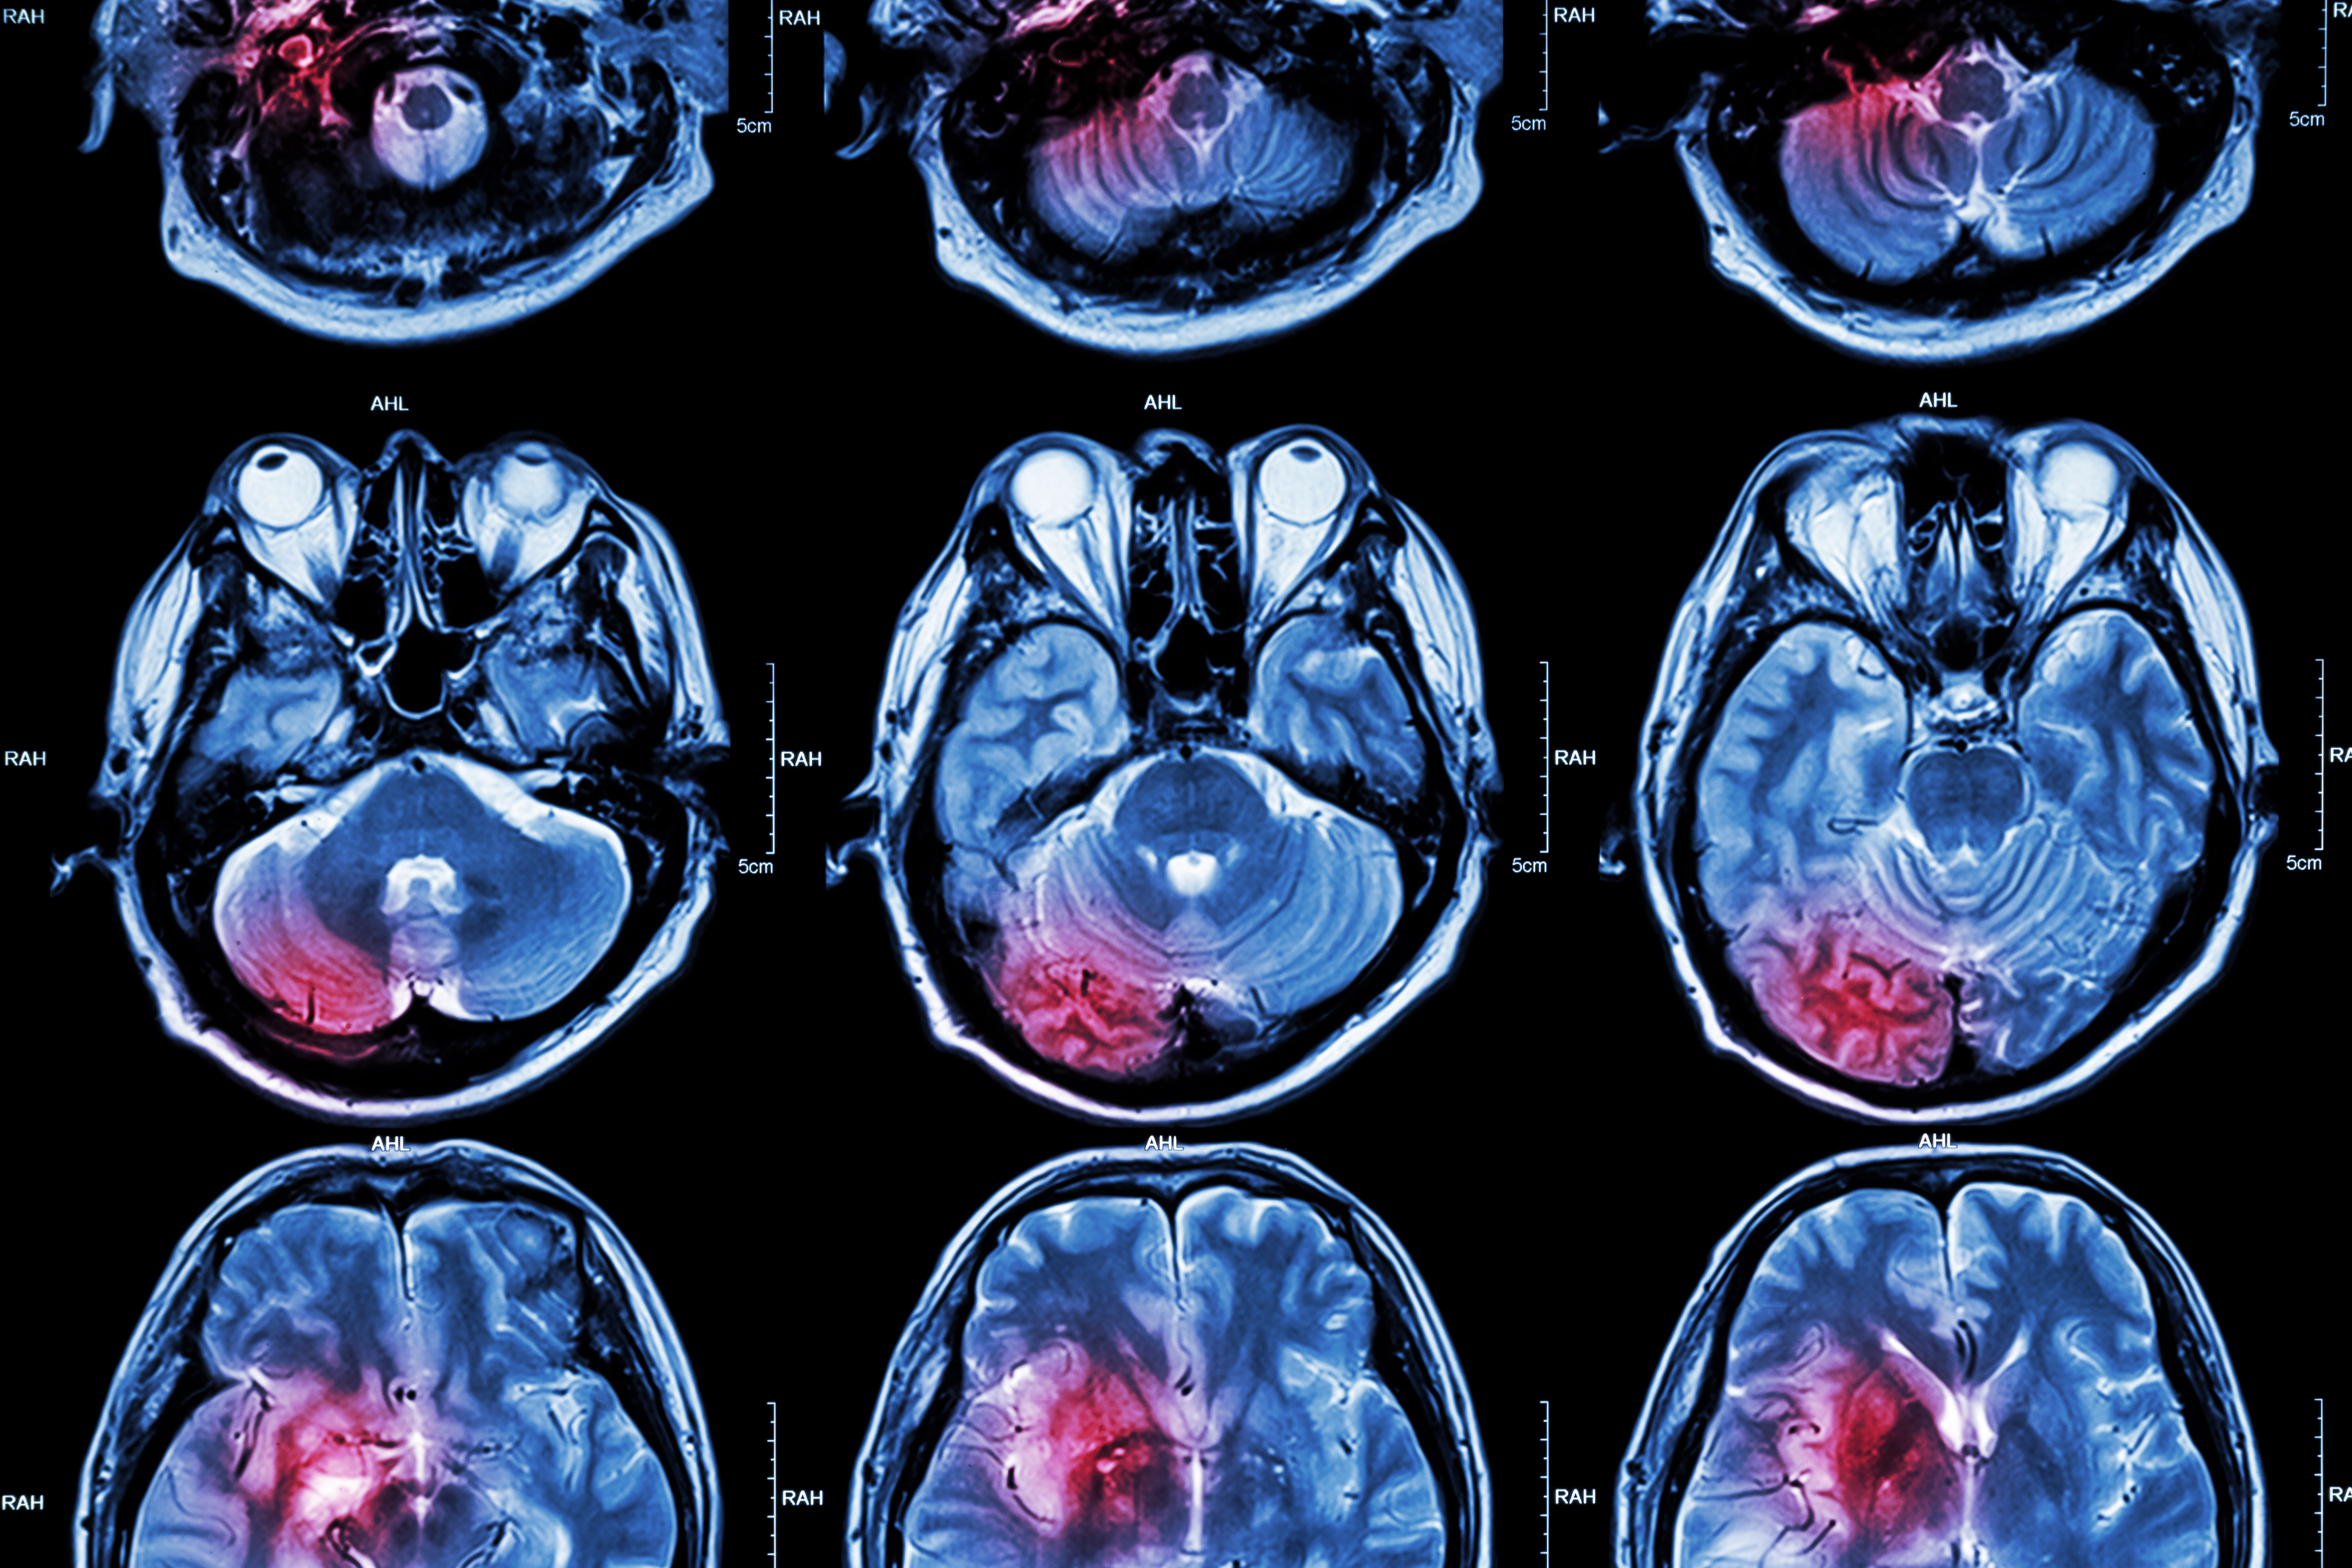

Although ischemic stroke is fairly rare as a cause of dizziness in the ED setting, it can be difficult to discern whether dizziness is caused by nonischemic factors -- a problem that presents a "diagnostic dilemma" for ED clinicians, Tegtmeyer and colleagues noted.

"This dilemma is further hindered by the poor sensitivity of CT and CTA for posterior fossa strokes," they wrote.

Previous research has suggested that MRI offers high sensitivity for detecting posterior fossa strokes, although conventional MRI may not be readily available in all practice settings, the group explained. That's why other imaging strategies such as portable MRI and CT perfusion could help, especially since they may have higher sensitivity than CT/CTA.